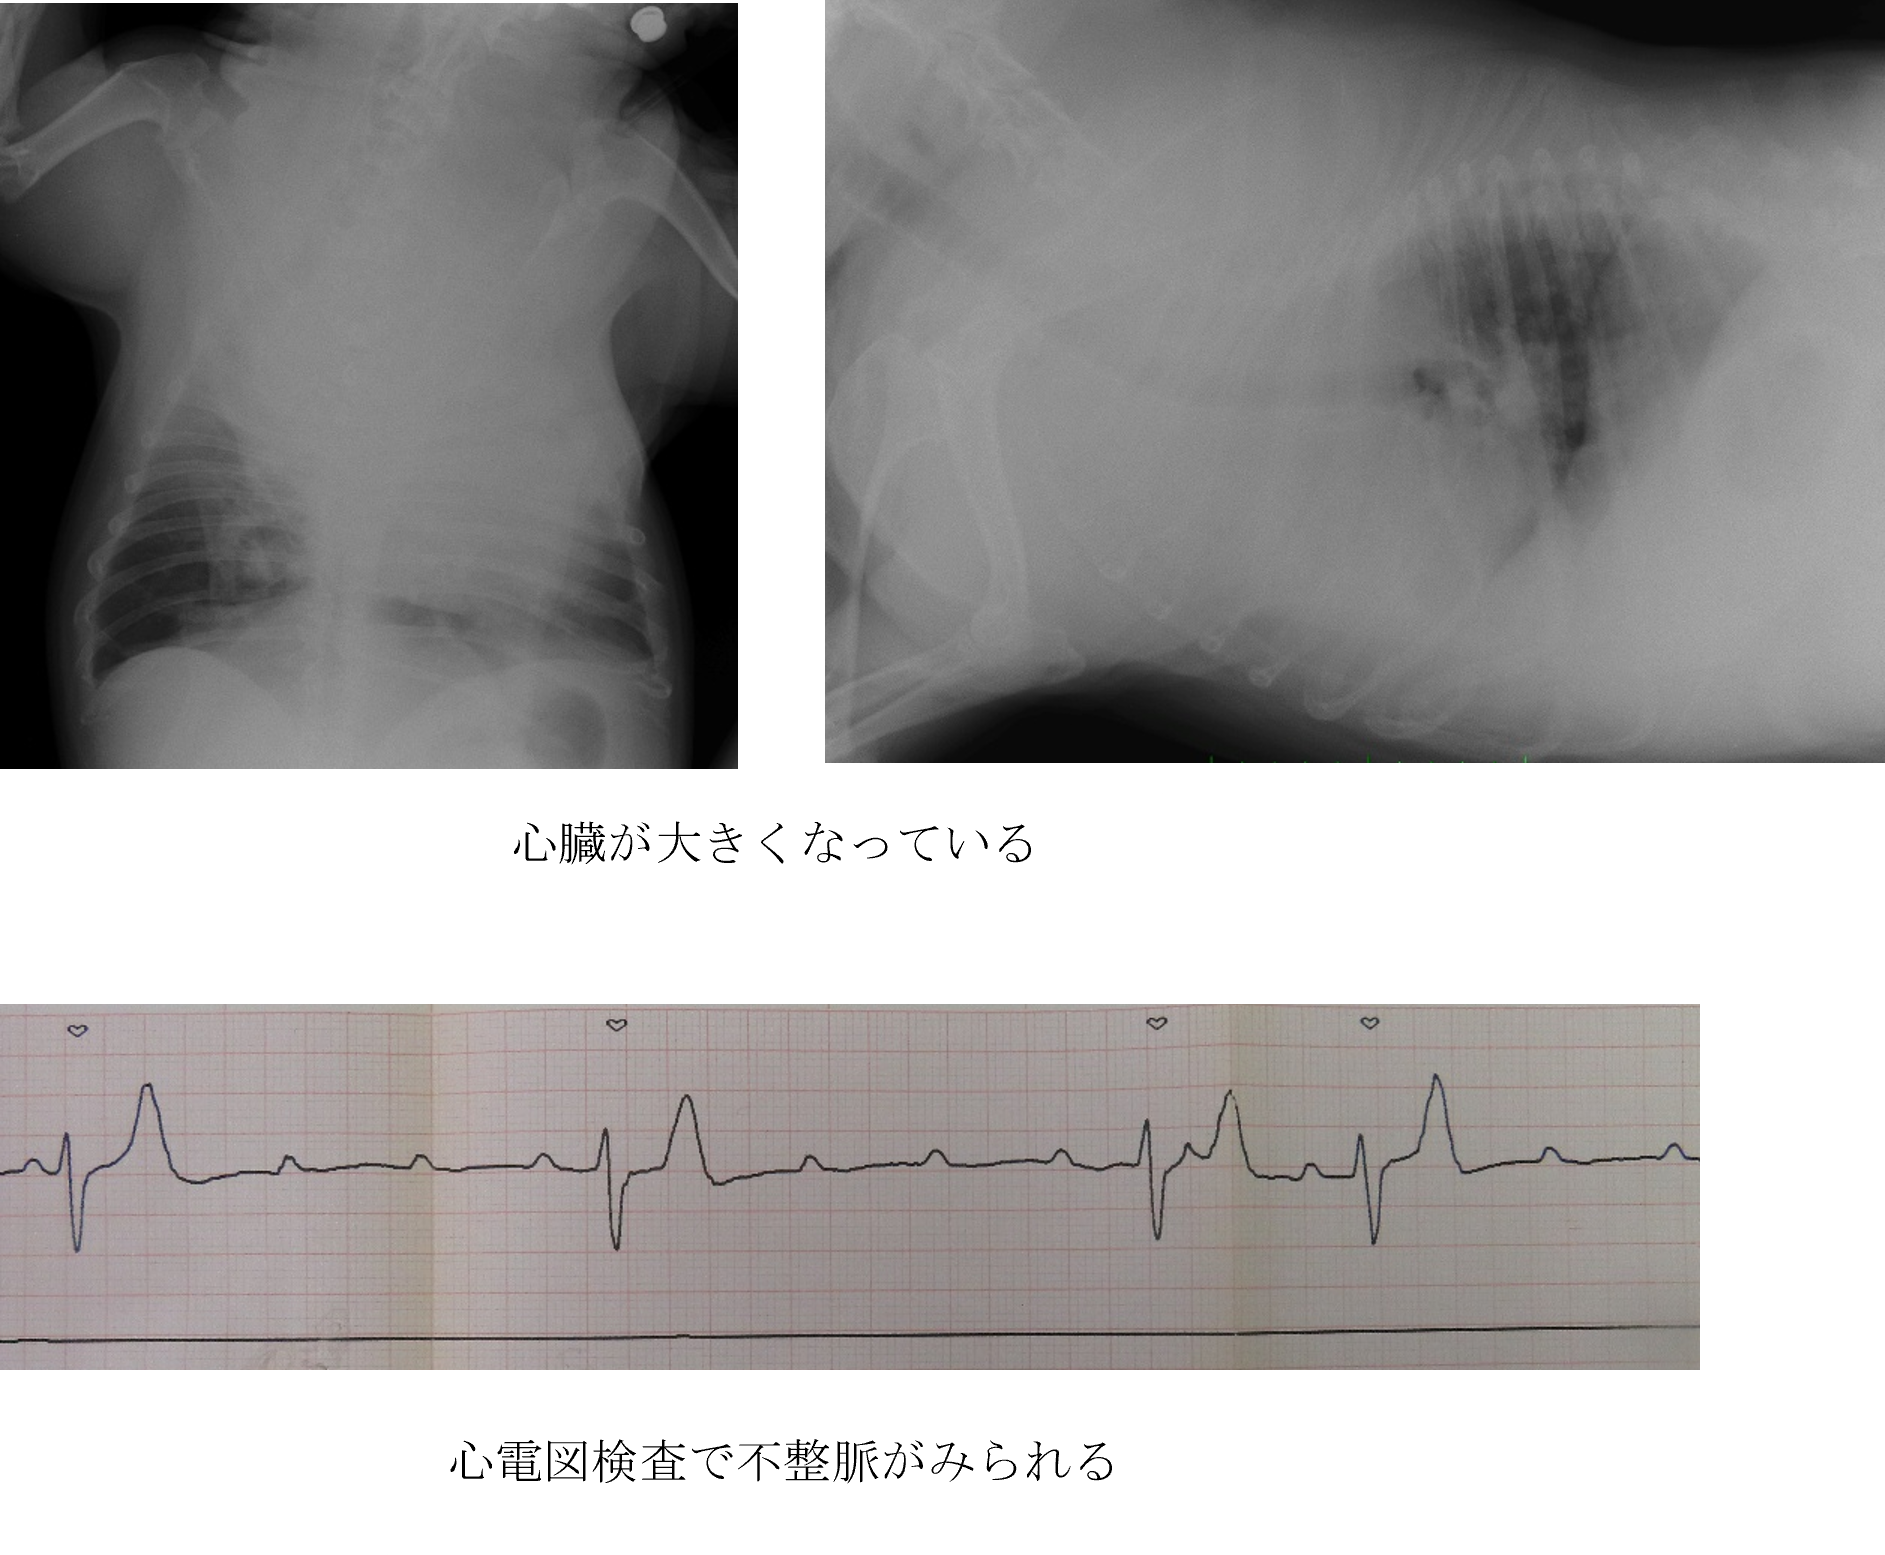

散歩中に歩かなくなり急に倒れた【不整脈原性右室心筋症】

散歩中に歩かなくなり、急に倒れた。

各種検査より、不整脈原性右室心筋症と診断しました。

ご家族と相談した結果、内科的治療(薬による治療)を行いました。

不整脈は改善して失神して倒れることはなくなりました。